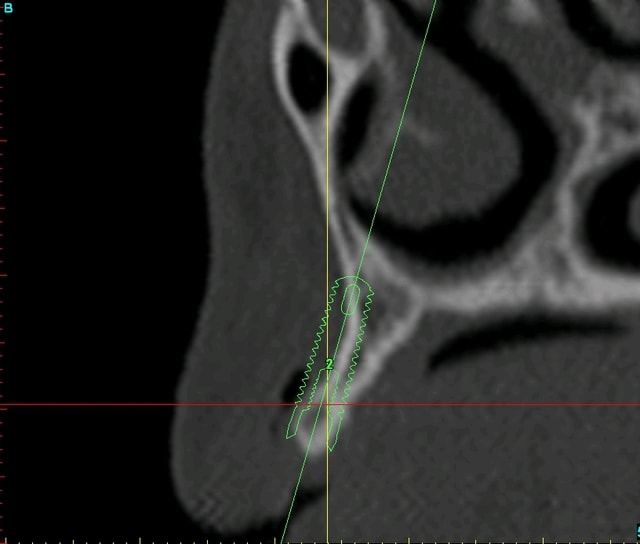

du coup, j'hésite entre 2 type d'interventions pour la pose des implants (mais là çà sera pas avant octobre...)

soit je retire les vis d'ostéosynthèse en faisant une toute petite incision en regard de chaque vis (ce qui me permettra de faire un "mini-lambeau" (séduisant vu que j'aimerai faire une mise en esthétique immédiate...))

soit je ré-ouvre tout en grand et là je reprofile un peu le nonos...

je vous remets les images avant/après pour un comparo...;-)

Planif euc3aq - Eugenol

Plan c8bcsp - Eugenol